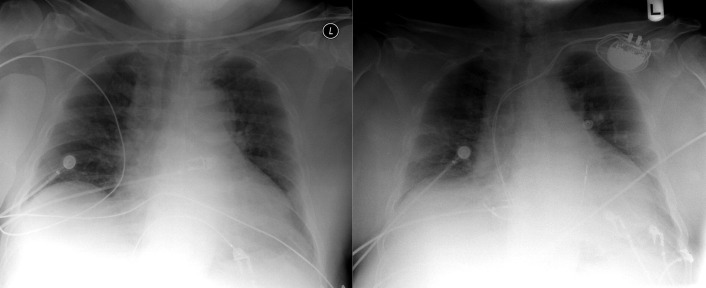

Chest radiography has a standard role in the identification of several potential complications such as pneumothorax, hemothorax, and several forms of malposition after insertion of pacemakers, implantable cardioverter defibrillators (ICDs), and cardiac resynchronization therapy devices.

Pacemaker leads are apparent, and ICDs are more obvious because of their larger coils. Coronary sinus leads for cardiac resynchronization therapy are finer leads.

Endocardial Pacer Leads

The position and integrity of endocardial pacer leads should be verified, especially when pacemaker dysfunction is clinically suspected ( Graphics 23-1 to 23-4 ; Figs. 23-1 to 23-15 ).The most common cause of pacemaker dysfunction that is apparent on the chest radiography is distal lead displacement/misplacement.